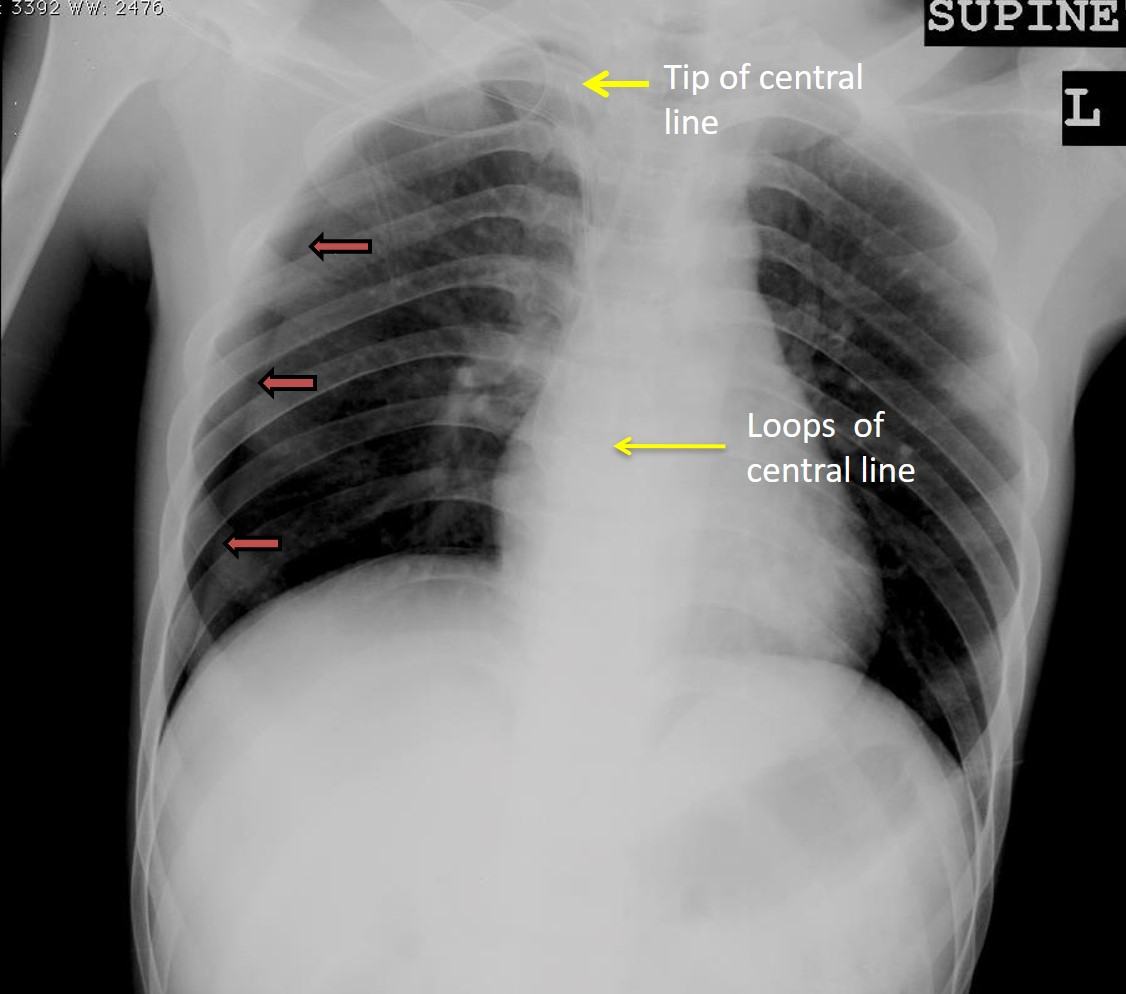

- Visualization of pleural lining on the right side (orange arrows) with no lung markings distal to this pleural lining in keeping with pneumothorax

- No mediastinal shift or flattening of hemidiaphragm to suggest tension pneumothorax

- The central line is seen forming a loop at atrial region and its tip seen over the upper mediastinal area (yellow arrows)

- No blunting of both costophrenic angle

Iatrogenic right pneumothorax post central venous catheter insertion